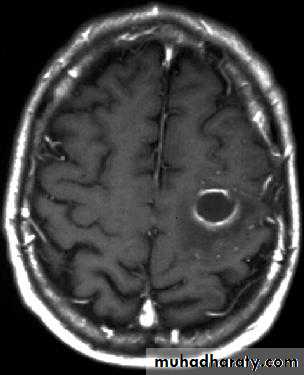

Brain Abscess CT with contrast

د.عبدالرحمن

• They will show a single (or multiple) space occupying lesion that is well delineated with an enhancing wall, with variable surrounding oedema.